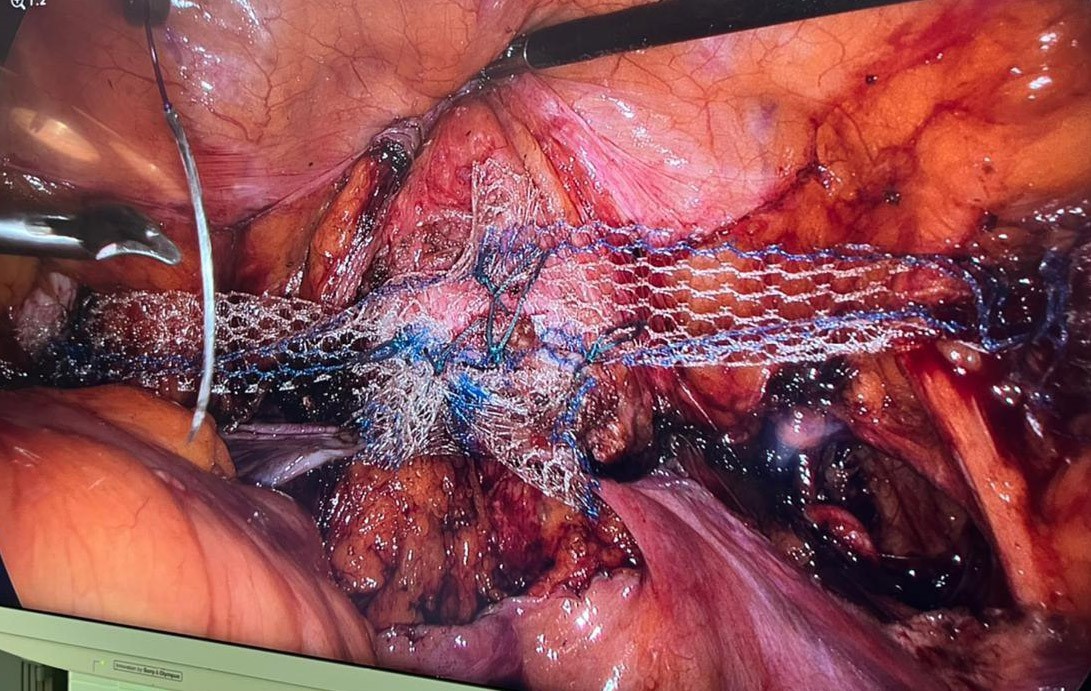

Второй, поперечный имплантат в виде ленты 4×15 см фиксировали центральной частью также к культе влагалища или шейки матки, а концами к гребенчатым связкам отдельными швами нерассасывающейся нитью (рис. 3, 4). Причём для обеспечения нормального физиологического положения культи влагалища или шейки матки перед этапом закрепления концов ленты второго имплантата ассистент хирурга трансвагинально фиксировал купол влагалища или шейку матки путём проталкивания в апикальном направлении.

Рис. 3. Второй, поперечный имплантат фиксируют концами к гребенчатым связкам отдельными швами нерассасывающейся нитью.

Fig. 3. The second transverse implant is fixed with the ends to the comb ligaments by separate sutures with a non-absorbable thread.

Рис. 4. Фиксируют поперечный имплантат центральной частью также к культе влагалища или шейки матки, а концами к гребенчатым связкам отдельными швами нерассасывающейся нитью.

Fig. 4. The transverse implant is fixed with the central part also to the stump of the vagina or cervix, and the ends to the comb ligaments with separate sutures with a non-absorbable thread.

Обращает на себя внимание техника выполнения операции, а именно конструкция и метод установления имплантатов. Мы показали, что конструкция из имплантатов, соединённых с фиксацией в центральной области, образует надёжную структуру, а каждый из них выполняет свою функцию поддержки органов малого таза, как вдоль (1-й имплантат), в области продольной оси сагиттальной плоскости, так и поперёк (2-й имплантат), в области поперечной оси (рис. 5). Такие действия хирурга и предлагаемая фиксация имплантатов способствуют предупреждению их смещения, скручивания и сморщивания, что повышает эффективность поддерживающего аппарата малого таза, обусловливает улучшение результата операции по ликвидации пролапса и обеспечивает долговременность лечебного эффекта.

Рис. 5. Конструкция из соединённых имплантатов, с фиксацией в центральной области, образует надёжную структуру, а каждый из них выполняет свою функцию поддержки органов малого таза, как вдоль (1-й имплантат), в области продольной оси сагиттальной плоскости, так и поперёк (2-й имплантат), в области поперечной оси.

Fig. 5. The design of connected implants, with fixation in the central area, forms a reliable structure, and each of them performs its function of supporting the pelvic organs, both along (1st implant), in the area of the longitudinal axis of the sagittal plane, and across (2nd implant), in the area of the transverse axis.